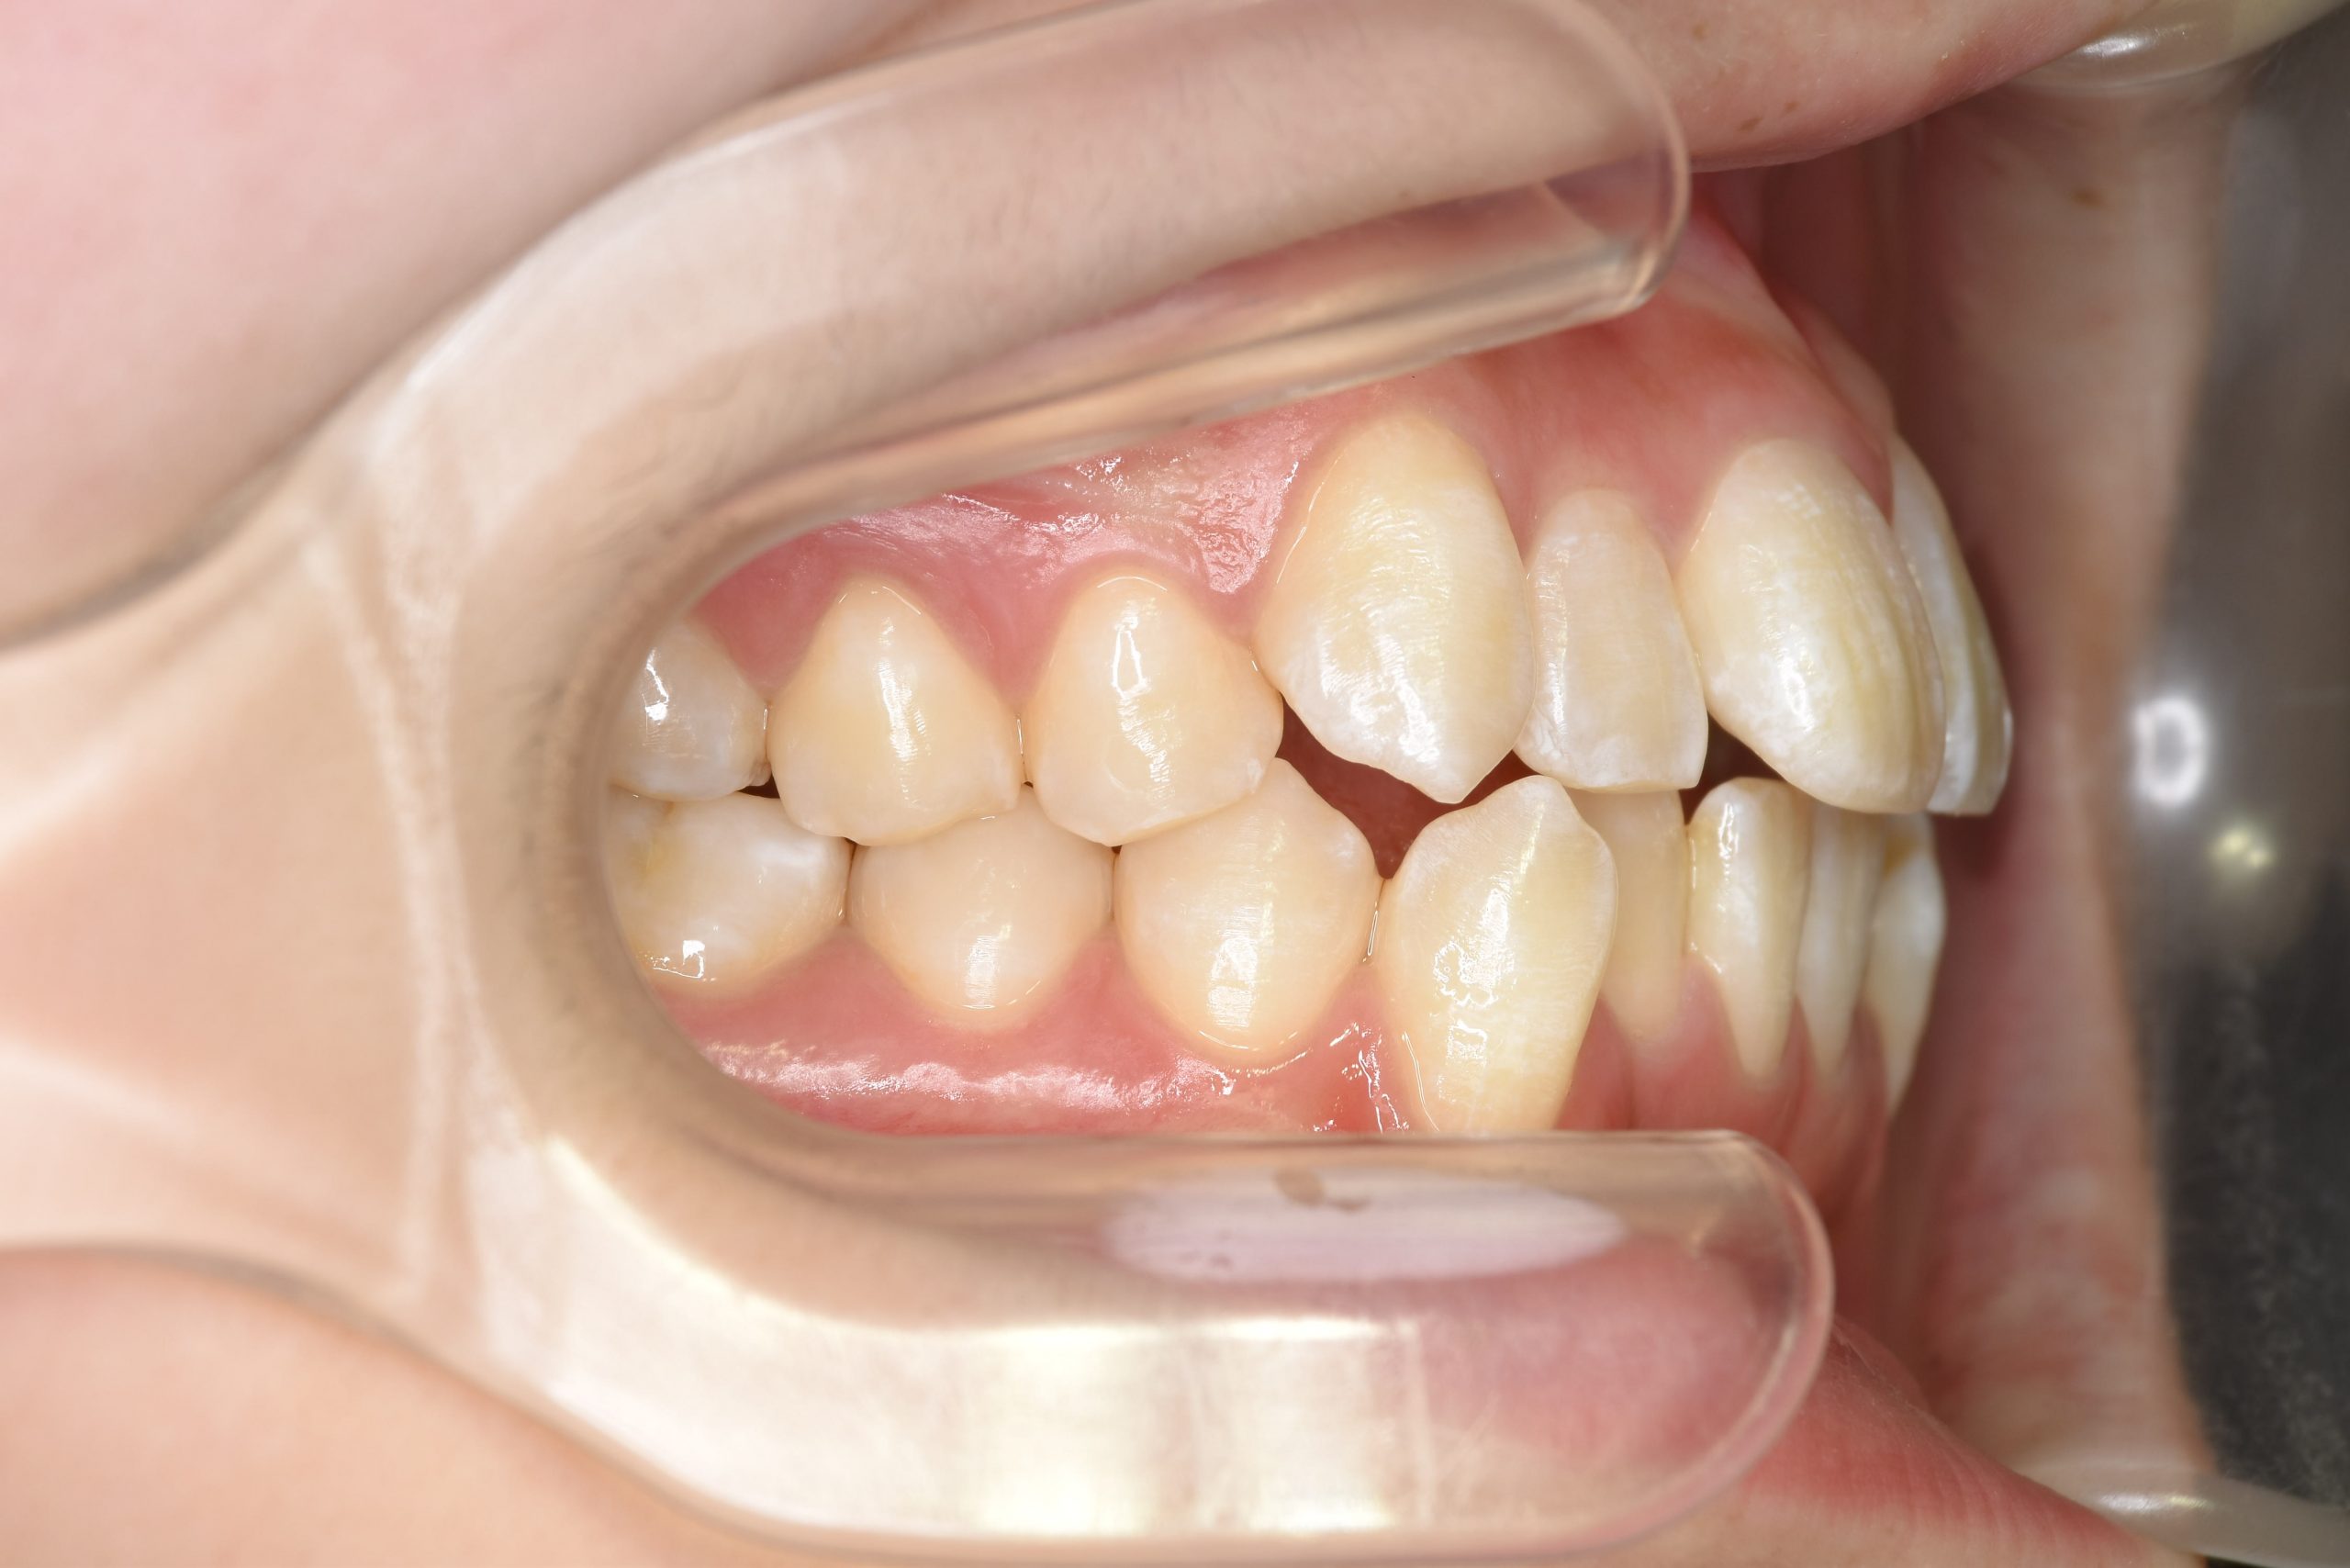

ビフォー

全顎ワイヤー矯正 症例_815

主訴 前歯の出っ歯|八重歯|下の歯のデコボコ|検診で噛み合わせが悪いと指摘されたこと

施術内容 成人矯正1期治療

治癒期間 1年4か月間

費用 954,800円(税込)